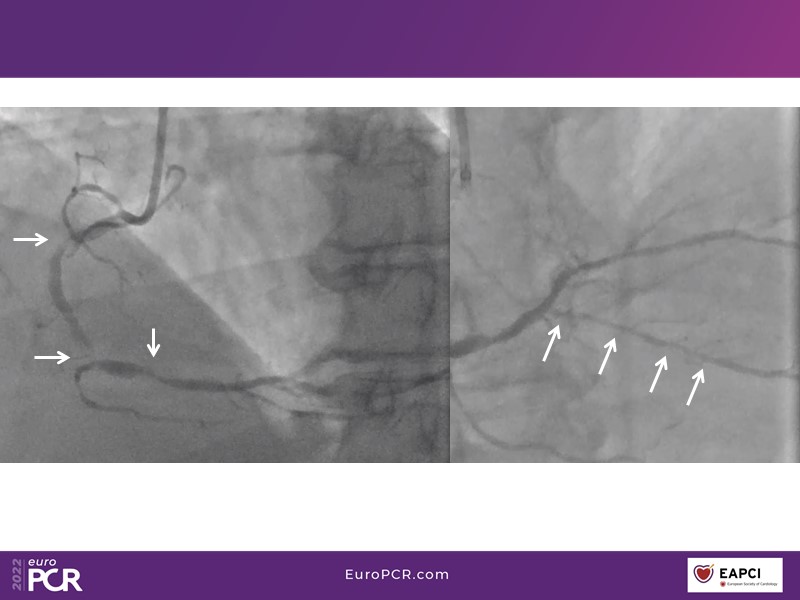

- To find out more about the application and mechanism of a sirolimus coated balloon for coronary artery disease treatment with case presentations in complex settings

- To understand how useful is a DES and DCB stent platform in complex coronary artery disease settings with case demonstrations and follow-up in diabetes mellitus